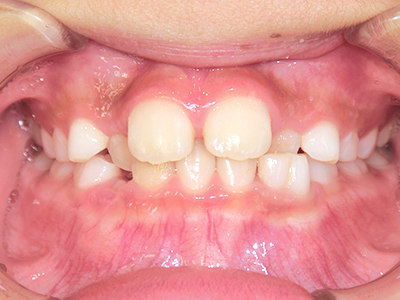

歯並びの相談に来られるお子様は、口呼吸をしているケースが多く、これが歯並びに大きな影響を与えています。

↓ - さまざまな不正咬合が生じる